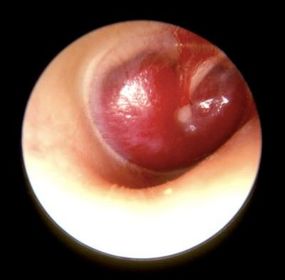

COLESTEATOMA SEGÚN EL EQUIPO

GLOMUS JUGULARE

MASTOIDITIS

OTITIS SEROSA MEDIA

POLIPO AUDITIVO